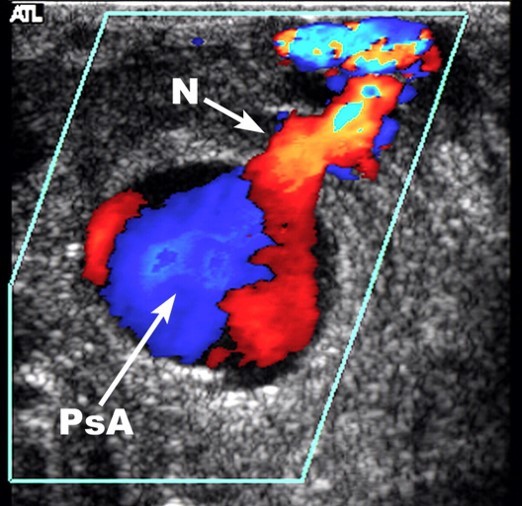

On the day post ablation Ms. X started complaining of groin tenderness. Examination revealed a preserved femoral pulse and a faint bruit that was not noted before. A groin ultrasound was ordered. The main finding is seen in the image below:

This is a pseudoaneurysm. There is a typical to and fro flow pattern in the neck. There is a typical ‘bubble’ with a ‘Yin-Yang’ flow pattern. This pseudoaneurysm measured about 1.2 cm. What would you do in this case?

A pseudoaneurysm of this size may close on its own. The risk of rupture from this a small pseudoaneurysm is rather low. However, ultrasound guided pseudoaneurysm compression is more definitive. Compression is even more likely to work in patients who will not need anticoagulation. Compression should be aimed at the neck, not the bubble. The compression should be done with the ultrasound probe in bouts of 10 minutes each, often for as much as 30 or more minutes. Compression is painful. Patients should receive an anxiolytic or systemic pain medication. They should receive local anesthesia.

If ultrasound guided compression fails (and it often does), the next option for treatment is thrombin injection. Injection is fairly straight forward and definitive. Pseudoaneurysm recurrence after thrombin injection is low. However, it may not be perfect for this pseudoaneurysm. This is where the theoretical hitch lies in this patient. In her case the pseudoaneurysm is very close to the common femoral artery. Despite lack of supporting literature, some would say that thrombin injected into this pseudoaneurysm may end up in the artery and may cause arterial thrombosis.